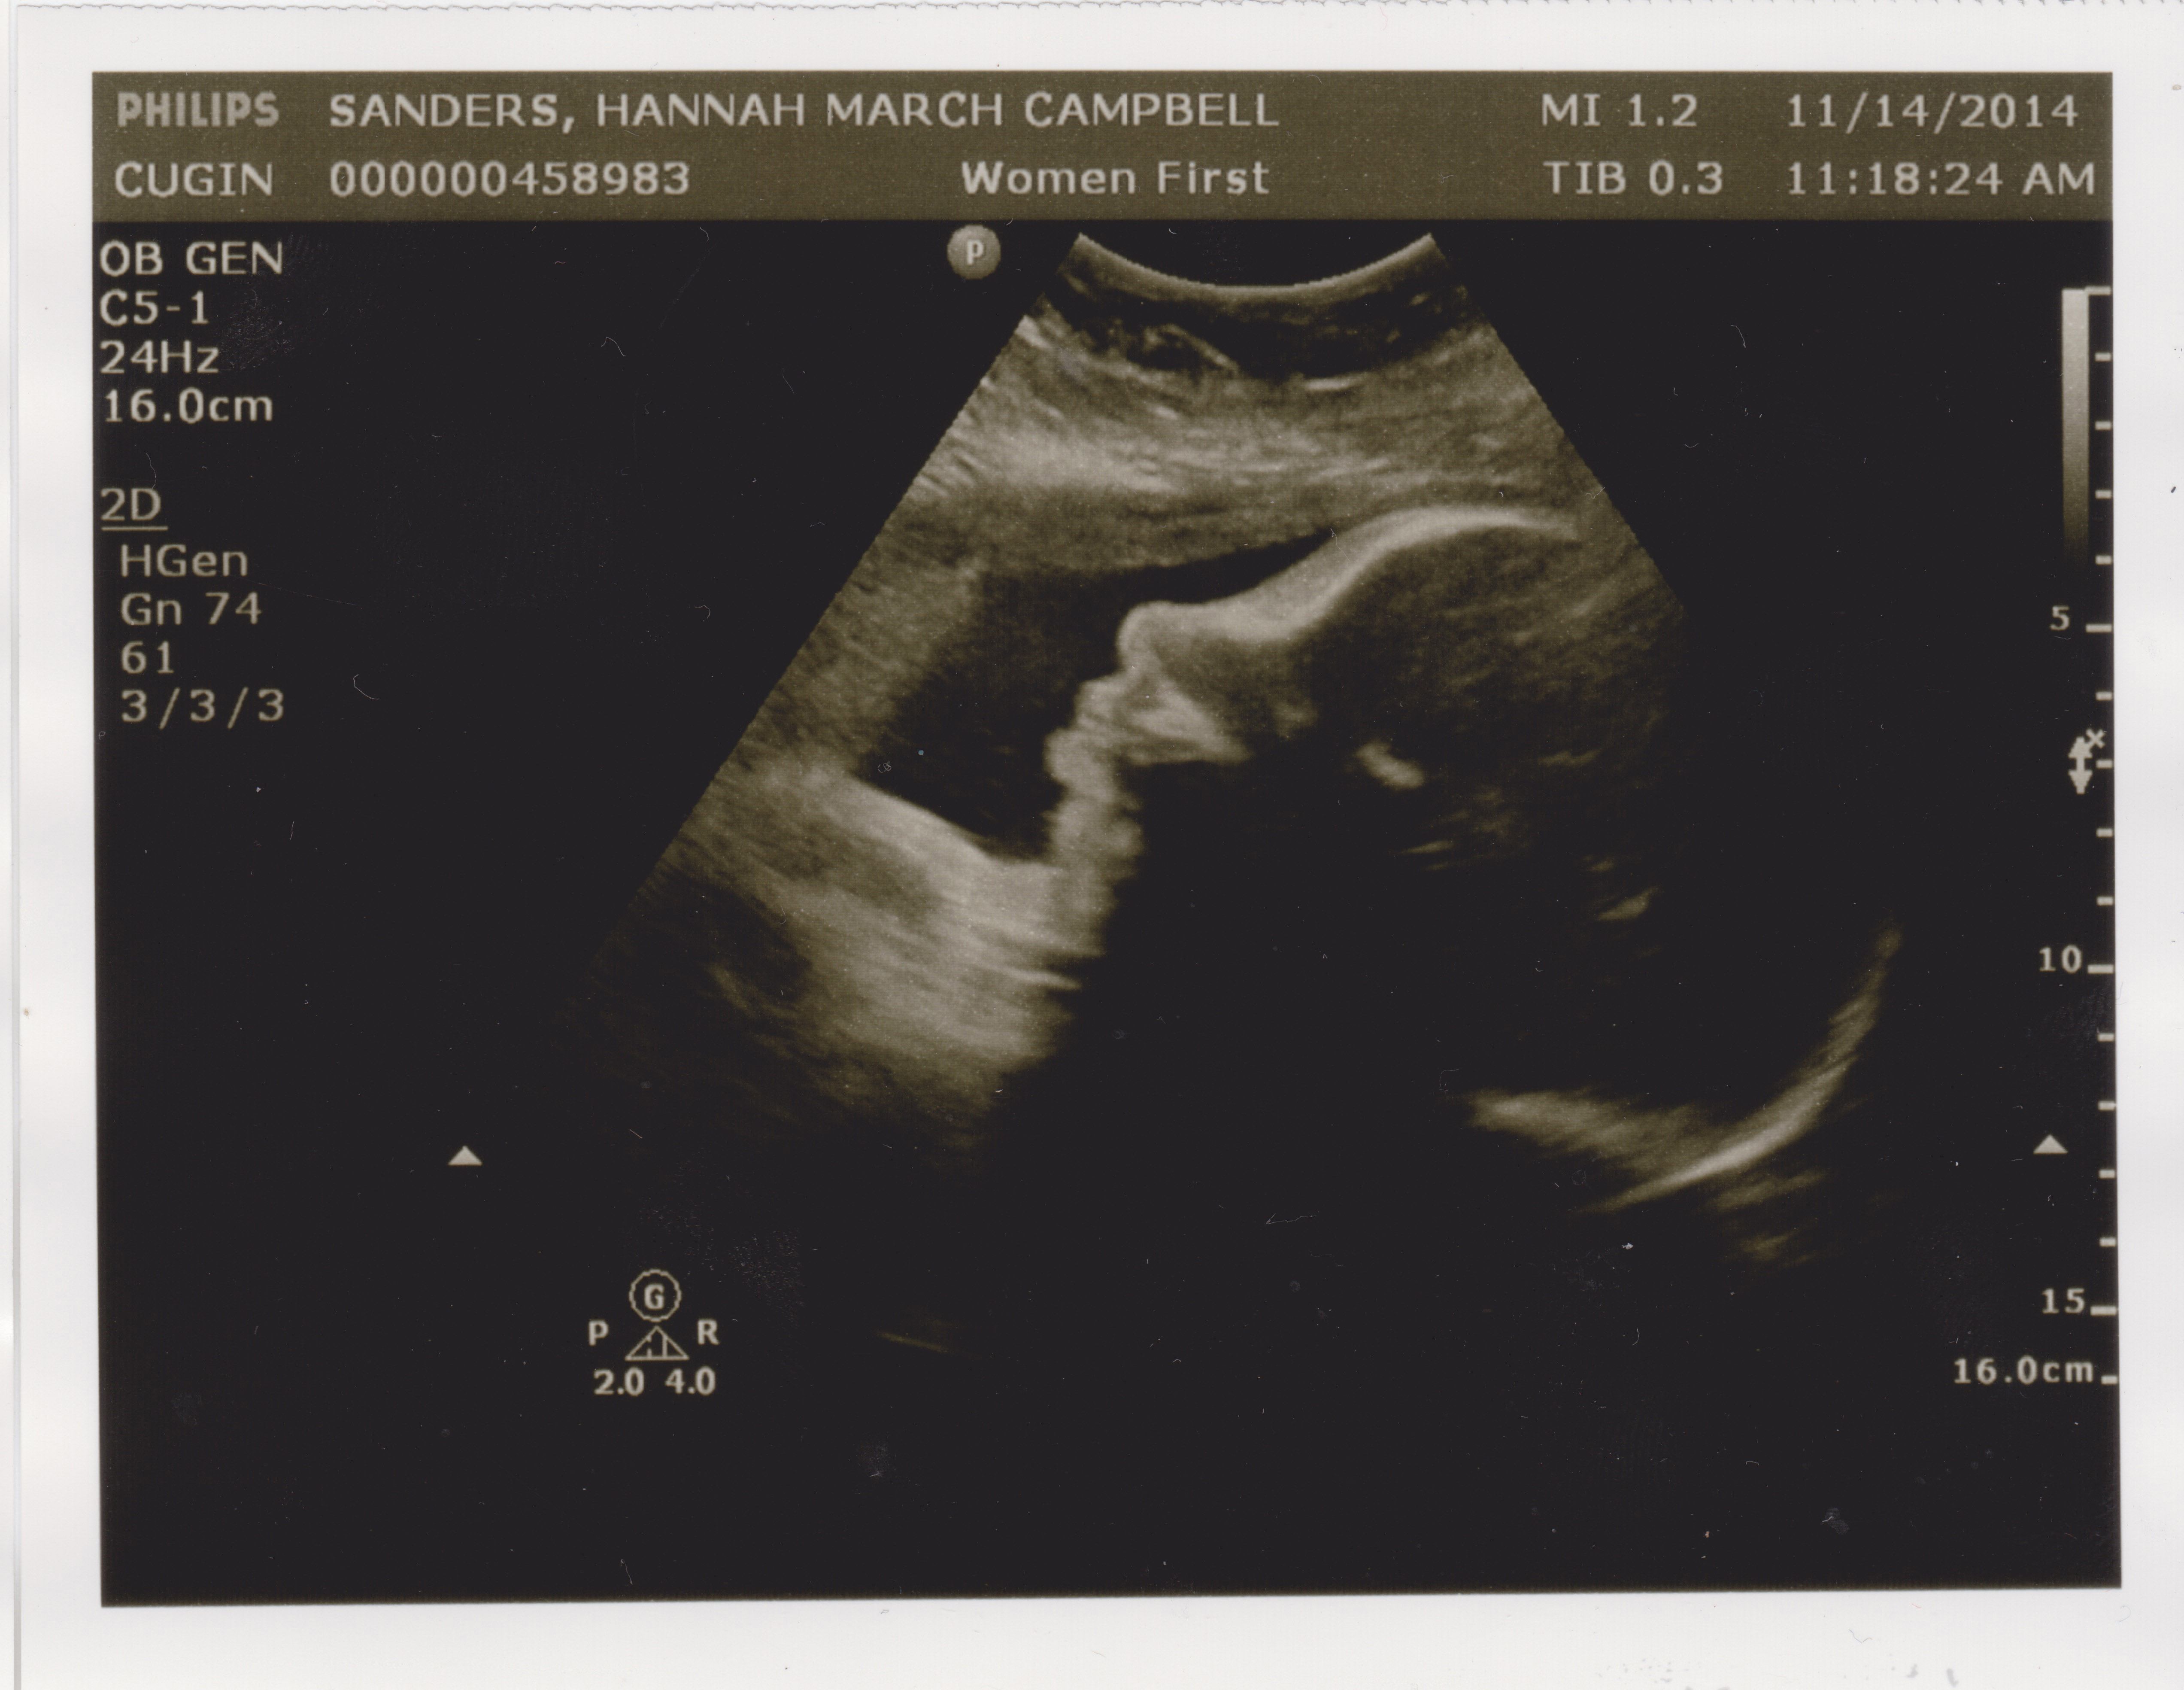

Another Friday, another doctor’s appointment. Today was Hannah’s second ultrasound in as many weeks, to check on the growth rate of the undersized nugget. In the last two weeks it’s gained a little less than half a pound, from 4lb. 5oz. to 4lb. 12oz. That was about a half pound less than the ultrasound tech. was hoping for, but Dr. Cugini doesn’t seem super concerned.

However, the baby is now under the 10th percentile for growth, so in order to prove everything’s OK, a new regimen begins. From here on in it’ll be two visits a week. Once a week we’ll go in for a BPP, an ultrasound that checks for growth and muscle-tone. Later in the week it’s another NST, the dreaded Non-Stress Test, where Hannah has air hockey paddles strapped to her belly for half an hour while the baby’s heartbeat blares like feedback at a death metal concert. Non-Stress indeed!